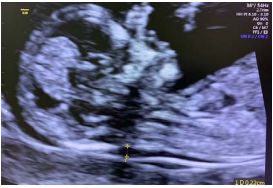

94 37 歲的孕婦第一次懷孕,在 13 週又 1 天時婦產科醫師為她安排了超音波胎兒掃描,檢查結果如下列 圖示。關於這項超音波檢查的敘述,何者最不適當? (A)第一孕期的唐氏症篩檢通常在妊娠 11 至 14 週間進行量測 (B)量測區域為 2.2 mm,有高風險的心臟結構異常、染色體異常,應建議進一步的檢查及遺傳諮詢 (C)量測區域結合母親血清妊娠相關血漿蛋白-A(PAPP-A)及游離性乙型人類絨毛性腺激素(free β-HCG)濃度即是第一孕期唐氏症篩檢的內容 (D)當偽陽率設定為 5%時,第一孕期唐氏症篩檢的偵測率約為 84%,與第二孕期篩檢的血清四指標偵 測率相當